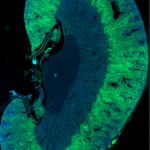

- High-quality histology and quantitative digital pathology

In vitro assays using human primary fibroblasts from different origins (renal, lung, cardiac or skin).

Validated surgical and ethical procedures on mice and rats to induce acute and chronic diseases.

Diabetic models to explore the pathology mechanisms including fibrosis, inflammation and glomerular alterations.